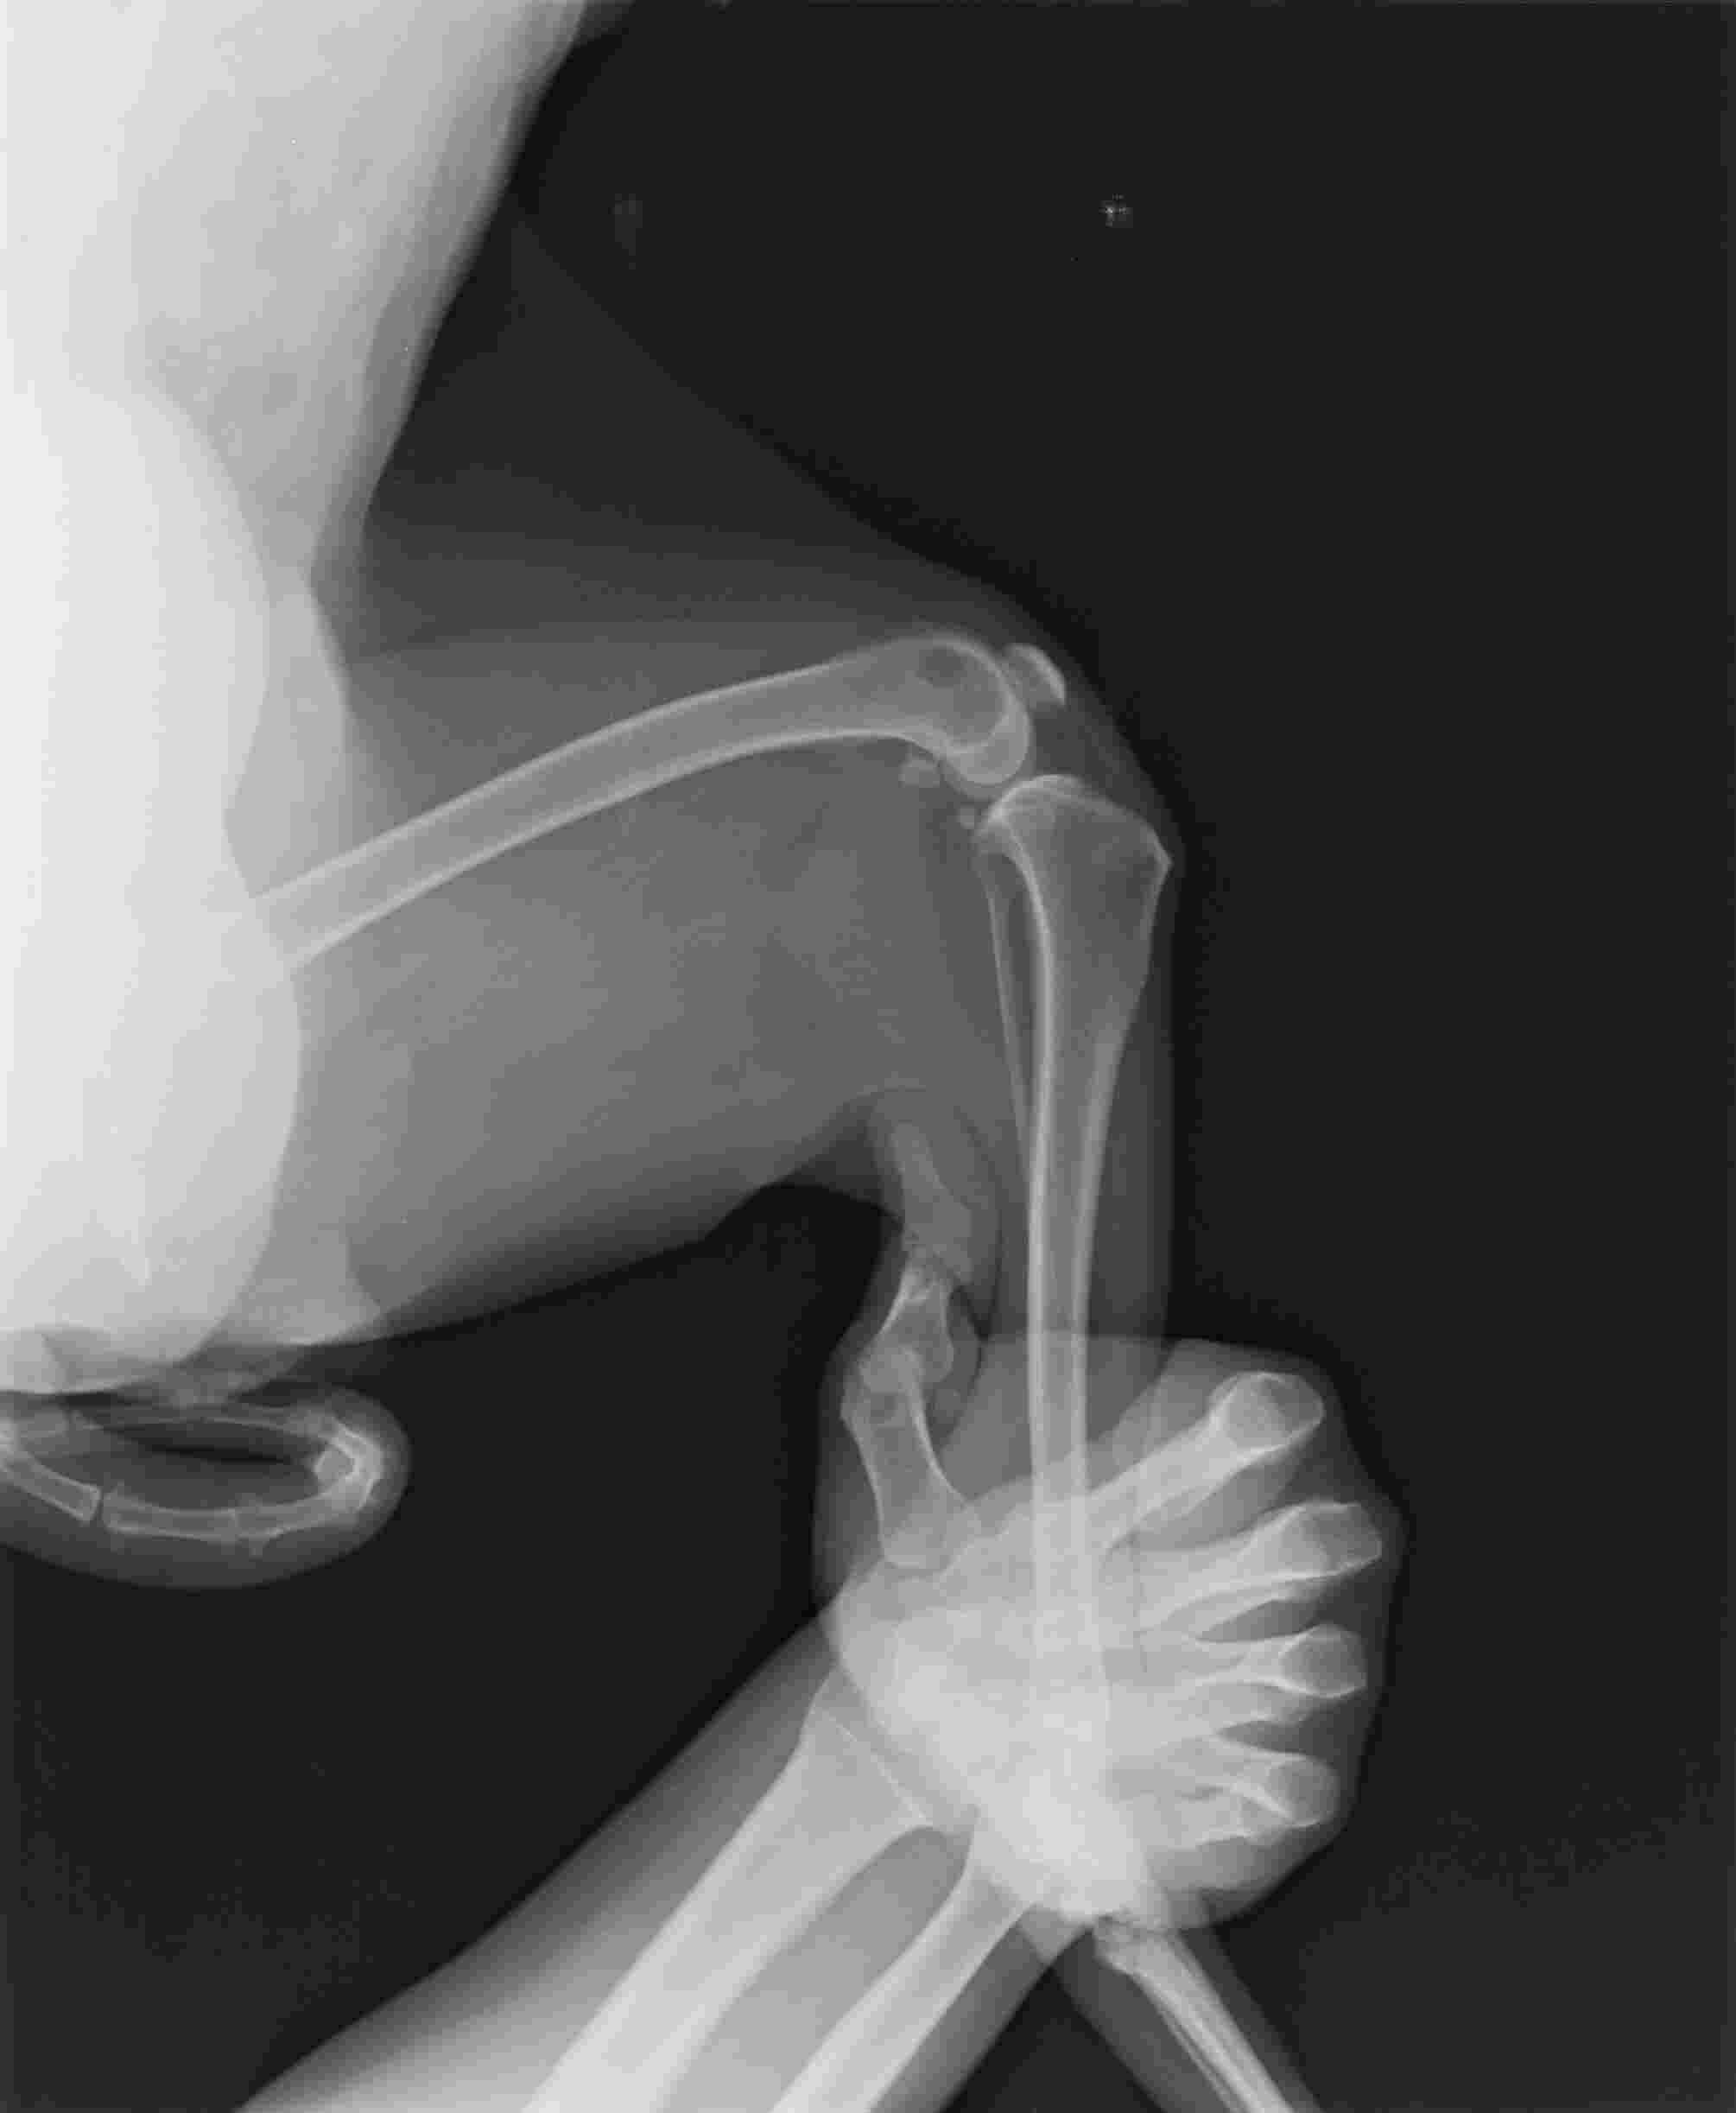

Hello, i have a husky female, she is 9 years old, in december she had the operation spayed and removal of a tumour in her breast in the same time both of them, since then the walking was not that good anhmore she barely could of and in the same time we went visitong her and she has arthrithis, now she barely can stay she can not walk anymore plase tell.me what can i do beside painkillers and supplements, i need some natural organic treatments a quick one please help

This question includes photos that may contain sensitive content. Click to view.